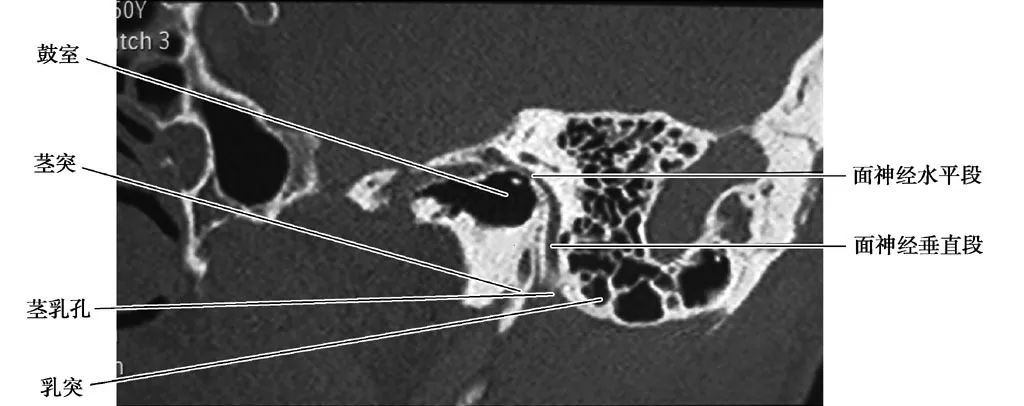

面神经水平段

(鼓室段)和垂直段(乳突段)(CT矢状面)

面神经垂直段